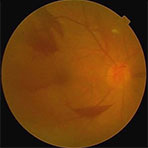

単純網膜症初期の単純網膜症の段階では、網膜の血管が傷んで血管瘤と呼ばれる「こぶ」が出来たり、網膜内に出血が発生します。更に硬性白斑と言う血液中の成分が網膜内に溜まってきたりします。

増殖前網膜症増殖前網膜症の段階に進むと、血管の傷みが更に進んで出血が増え、血管が詰まった所に軟性白斑という白い綿の様なものが出来ます。軟性白斑が多発している場合は、病気の程度は悪いと言えます。

増殖網膜症増殖網膜症に進むと、網膜から硝子体に向かって新生血管が伸びてきます。やっつけ仕事で作られた新生血管が破れると、硝子体出血が起こります。また、硝子体に繊維性の膜が出来て来ます。

これを増殖膜と言って厄介な膜です。その膜は眼内で収縮したりして、健康な網膜を引っ張ると網膜剥離が発生します。

糖尿病網膜症の検査画像